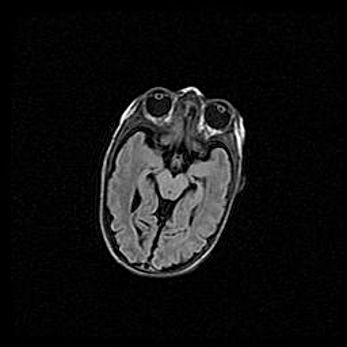

Церебральная ишемия II.

Возраст: 5 дней

Вес: 3400 г

Пол: женский

Окружность головы: 35 см

Срок гестации: 39 недель

Церебральная ишемия – это заболевание, характеризующееся недостаточностью (гипоксией) либо полным прекращением (аноксией) снабжения мозга кислородом по причине закупорки одного или нескольких сосудов. Это приводит к  что метаболическим расстройствам различной степени тяжести в тканях головного мозга, развитию коагуляционных некрозов и гибели нейронов.